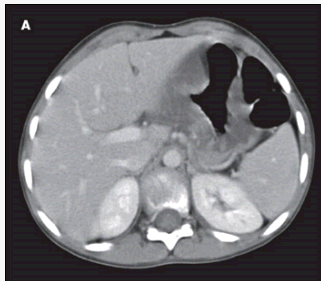

Vital signs were normal. An initial complete blood cell (CBC) count showed a white blood cell count of 18,000/μL, with 20% bands. Results of a chemistry panel were normal. Stool was positive for occult blood. A CT scan showed marked gastric wall thickening measuring 18 mm (A and B). The patient was admitted to the hospital. Results of another CBC count with differential and a second chemistry panel as well as a hepatic panel were normal. Stool was still positive. Her IgA level was 542 mg/dL (normal range, 100 to 200 mg/dL). Results of an upper endoscopy with biopsy were normal, without pathology. Five days after admission, the patient's ankles and knees became swollen. The next day, purpuric lesions developed on her feet and legs (C). A dermatologist who examined the patient diagnosed Henoch-Schönlein purpura (HSP). Although the parents refused a skin biopsy, the child's clinical presentation, elevated IgA level, and rash all pointed to this diagnosis.

The presentation of HSP varies with each patient. Clinical manifestations of this IgA-mediated vasculitis primarily include palpable purpura, arthralgia, arthritis, abdominal pain, GI bleeding, and nephritis. Abdominal pain with concomitant hematochezia affects more than half of patients with HSP and may be the presenting complaint. The abdominal pain is often sharp and colicky and results from submucosal and subserosal hemorrhage and edema, with thrombosis of the microvasculature in the gut. Gastric wall thickening has not been reported as a manifestation of HSP. This finding may be an early clue to the diagnosis of HSP in children with abdominal pain who present without the characteristic purpuric lesions.